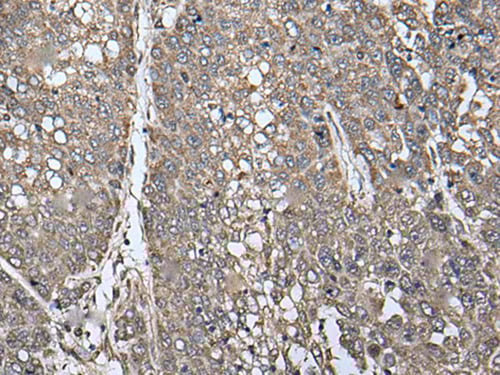

IHC (Immunohiostchemistry)

(The image on the left is immunohistochemistry of paraffin-embedded Human esophagus cancer tissue using ATAD1 Antibody at dilution 1/100, on the right is treated with fusion protein. (Original magnification: x200))